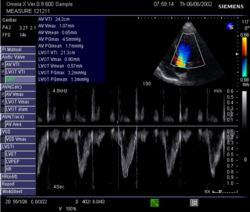

Doppler signal in the left ventricular outflow tract: Velocity Time Integral (VTI)

This method uses ultrasound and the Doppler effect to measure cardiac output. The blood velocity through the heart causes a Doppler shift in the frequency of the returning ultrasound waves. This shift can then be used to calculate flow velocity and volume, and effectively cardiac output, using the following equations:[citation needed]

• [math]\displaystyle{ Q = SV \times HR }[/math]

• [math]\displaystyle{ SV = VTI \times CSA }[/math]

• [math]\displaystyle{ CSA = \pi r^2 }[/math]

where:

• CSA is the valve orifice cross sectional area,

• r is the valve radius, and,

• VTI is the velocity time integral of the trace of the Doppler flow profile.